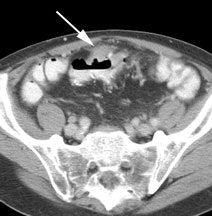

Initial staging for extrahepatic metastases: The patient below underwent FDG PET imaging to assess for extrahepatic metastatic disease prior to definitive surgical intervention. The PET exam demonstrates uptake within two hepatic metastases (black arrows on PET scan and yellow arrows on CT images) and in the patients primary colon cancer (blue arrow on PET scan and white arrow on CT image). No other sites of abnormal tracer uptake were identified which supports surgical intervention in this case. |

Initial staging for colorectal carcinoma: The patient below presented for evaluation of colorectal carcinoma. The CT scan demonstrated a large liver mass (red arrows) compatible with metastatic disease. The patient's cecal mass (black arrow on PET scan) was not detected on the CT study (white arrow). No other lesions were identified on the PET scan. |